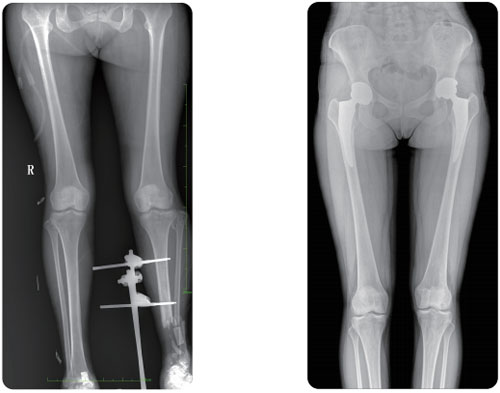

Visualizing intramedullary nail

Intramedullary nailing is the most common minimally invasive surgery in orthopedics.

PLX8600 could be able to provide large filed of view for better demonstrating fracture site and nail position, e.g. those IM nails implanted in femur and humerus in particular.

One photograph for both lower limbs, no additional stitching required. Measuring funciton is also available, which is easy for radiologist to record the data for accurate diagnosis.